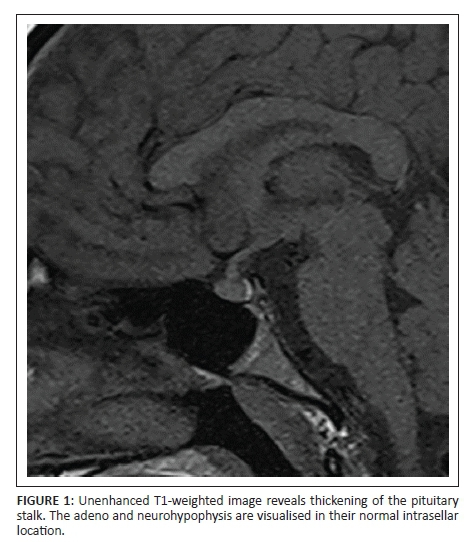

T1-weighted non-contrast MRI demonstrated thickening of the pituitary stalk (Figure 1). Dynamic contrast-enhanced T1 sagittal (Figure 2a) and coronal (Figure 2b) images of the sellar and parasellar regions revealed a hypoenhancing microadenoma in the anterior aspect of the pituitary stalk. This tumour was not connected to the intrasellar pituitary gland. The intrasellar pituitary gland was normal in height and signal intensity on both pre- and post-contrast images with a flat superior contour. The parasellar regions were normal bilaterally. The optic chiasm displayed normal morphology with no evidence of compression, and the sphenoid sinus and clivus were normal in appearance.

On unenhanced scans, stalk adenomas manifest as thickening of the stalk. The normal stalk measures 3.25 ± 0.56 mm at the level of optic chiasma and tapers down to measure 1.91 ± 0.4 mm at its pituitary insertion.7 After the administration of gadolinium, these tumours typically demonstrate hypo or delayed enhancement, relative to the normal pituitary, and dynamic contrast-enhanced MRI is the imaging modality of choice for their diagnosis.